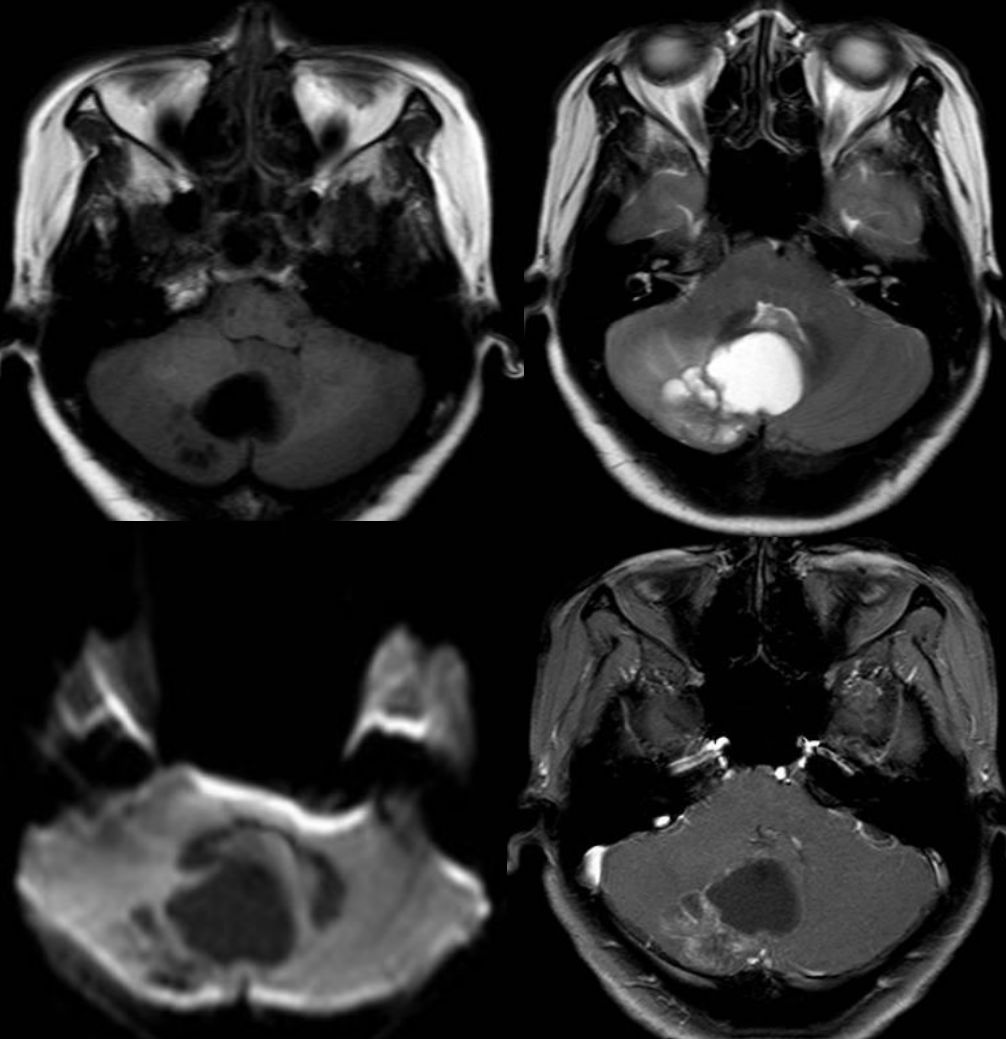

病例9

52岁,丙型肝炎患者,进行肝移植治疗肝硬化后使用免疫*制剂抑**等(他克莫司、霉酚酸酯、强的松)治疗。治疗3个月后出现间歇性头痛,复视(多为下视时出现),步态不稳,无全身症状。查体:血压136/73mmHg。眼球震颤,步态共济失调,腱反射正常。

答案:他克莫司相关神经毒性致脑干损伤。

补充辅助检查:血沉阴性,C-反应蛋白,艾滋病毒、半乳甘露聚糖、1,3-b-D-葡聚糖、隐球菌,结核均阴性。脑脊液中有1个白细胞,蛋白质101 mg/dL,革兰氏阴性染色,细菌性真菌培养,EB病毒,巨细胞病毒,单纯疱疹病毒,人类疱疹病毒6型,JC病毒,以及寡克隆带均阴性。免疫球蛋白G指数为正常。胸片呈阴性。脑PET扫描未发现PET摄取异常。在患者住院期间,他克莫司的治疗剂量为6.3~9.0ng/ ml。经治医生不排除他克莫司导致脑干脑炎的可能,并将药物改为环孢菌素。患者入院2周和6周各进行了一次MRI 检查,结果显示脑干病变较前好转 (图B、C)。6个月后随访,患者的神经系统检查和MRI 均未见明显异常。B为他克莫司停药后2周MRI。C为 6周后脑磁共振Flair图像。

他克莫司是抑制神经钙蛋白磷酸酶活性和T淋巴细胞化的免疫*制剂抑**。可引发一系列神经系统的不良反应,包括轻微头痛、震颤痫性发作、皮质性失明和昏迷,且不良反应的发生与他克莫司剂量无相关性。

当患者出现T2及Flair序列的脑桥高信号时,要考虑到他克莫司神经毒性导致脑干脑炎的可能。